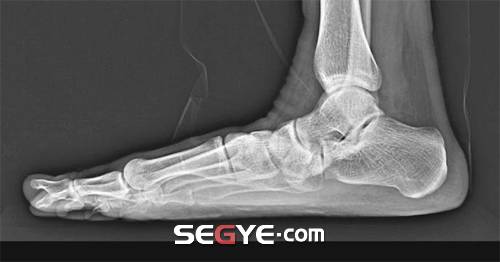

일반적으로 정상적인 발은 발바닥 안쪽에 움푹 들어간 아치(arch)가 있다. 적당한 크기의 아치는 걸을 때 발에 전달되는 충격을 줄여주는 쿠션 역할을 하고 추진력을 만들어줘 보행에 도움을 준다.

평발은 발바닥의 아치가 비정상적으로 낮거나 없는 모든 종류의 발을 지칭하는데 발바닥이 납작한 평발은 누구나 쉽게 구분할 수 있다. 하지만 실제로는 평발이면서도 평발인지 모르고 평생을 사는 경우가 많은 것. 이런 숨어 있는 평발을 ‘유연성 평발’이라 부른다.

유연성 평발의 경우 보통 땐 아치가 유지되기 때문에 옆에서 보거나 앉아서 발바닥을 뒤집어 보았을 때는 구분이 어렵다. 유연성 평발은 체중이 실릴 때만 평발이 되는데, 보행 시 아치가 없어진 상태에서 발바닥 전체가 지면에 닿아 완충 기능을 제대로 못하는 것. 조금만 걸어도 쉽게 피로해지거나 발이 아픈 경우도 이 때문이다.